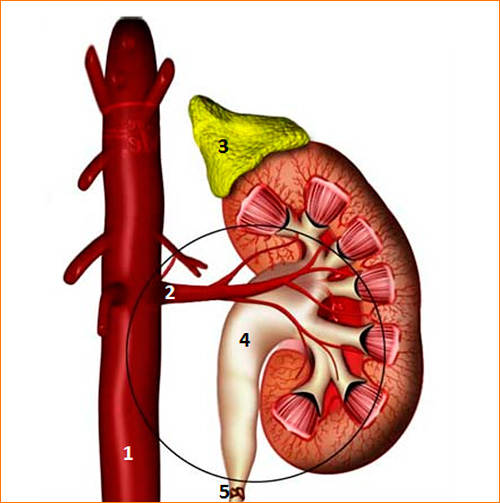

Рефлюксирующий мегауретер: Визуализация и медицинские изображения